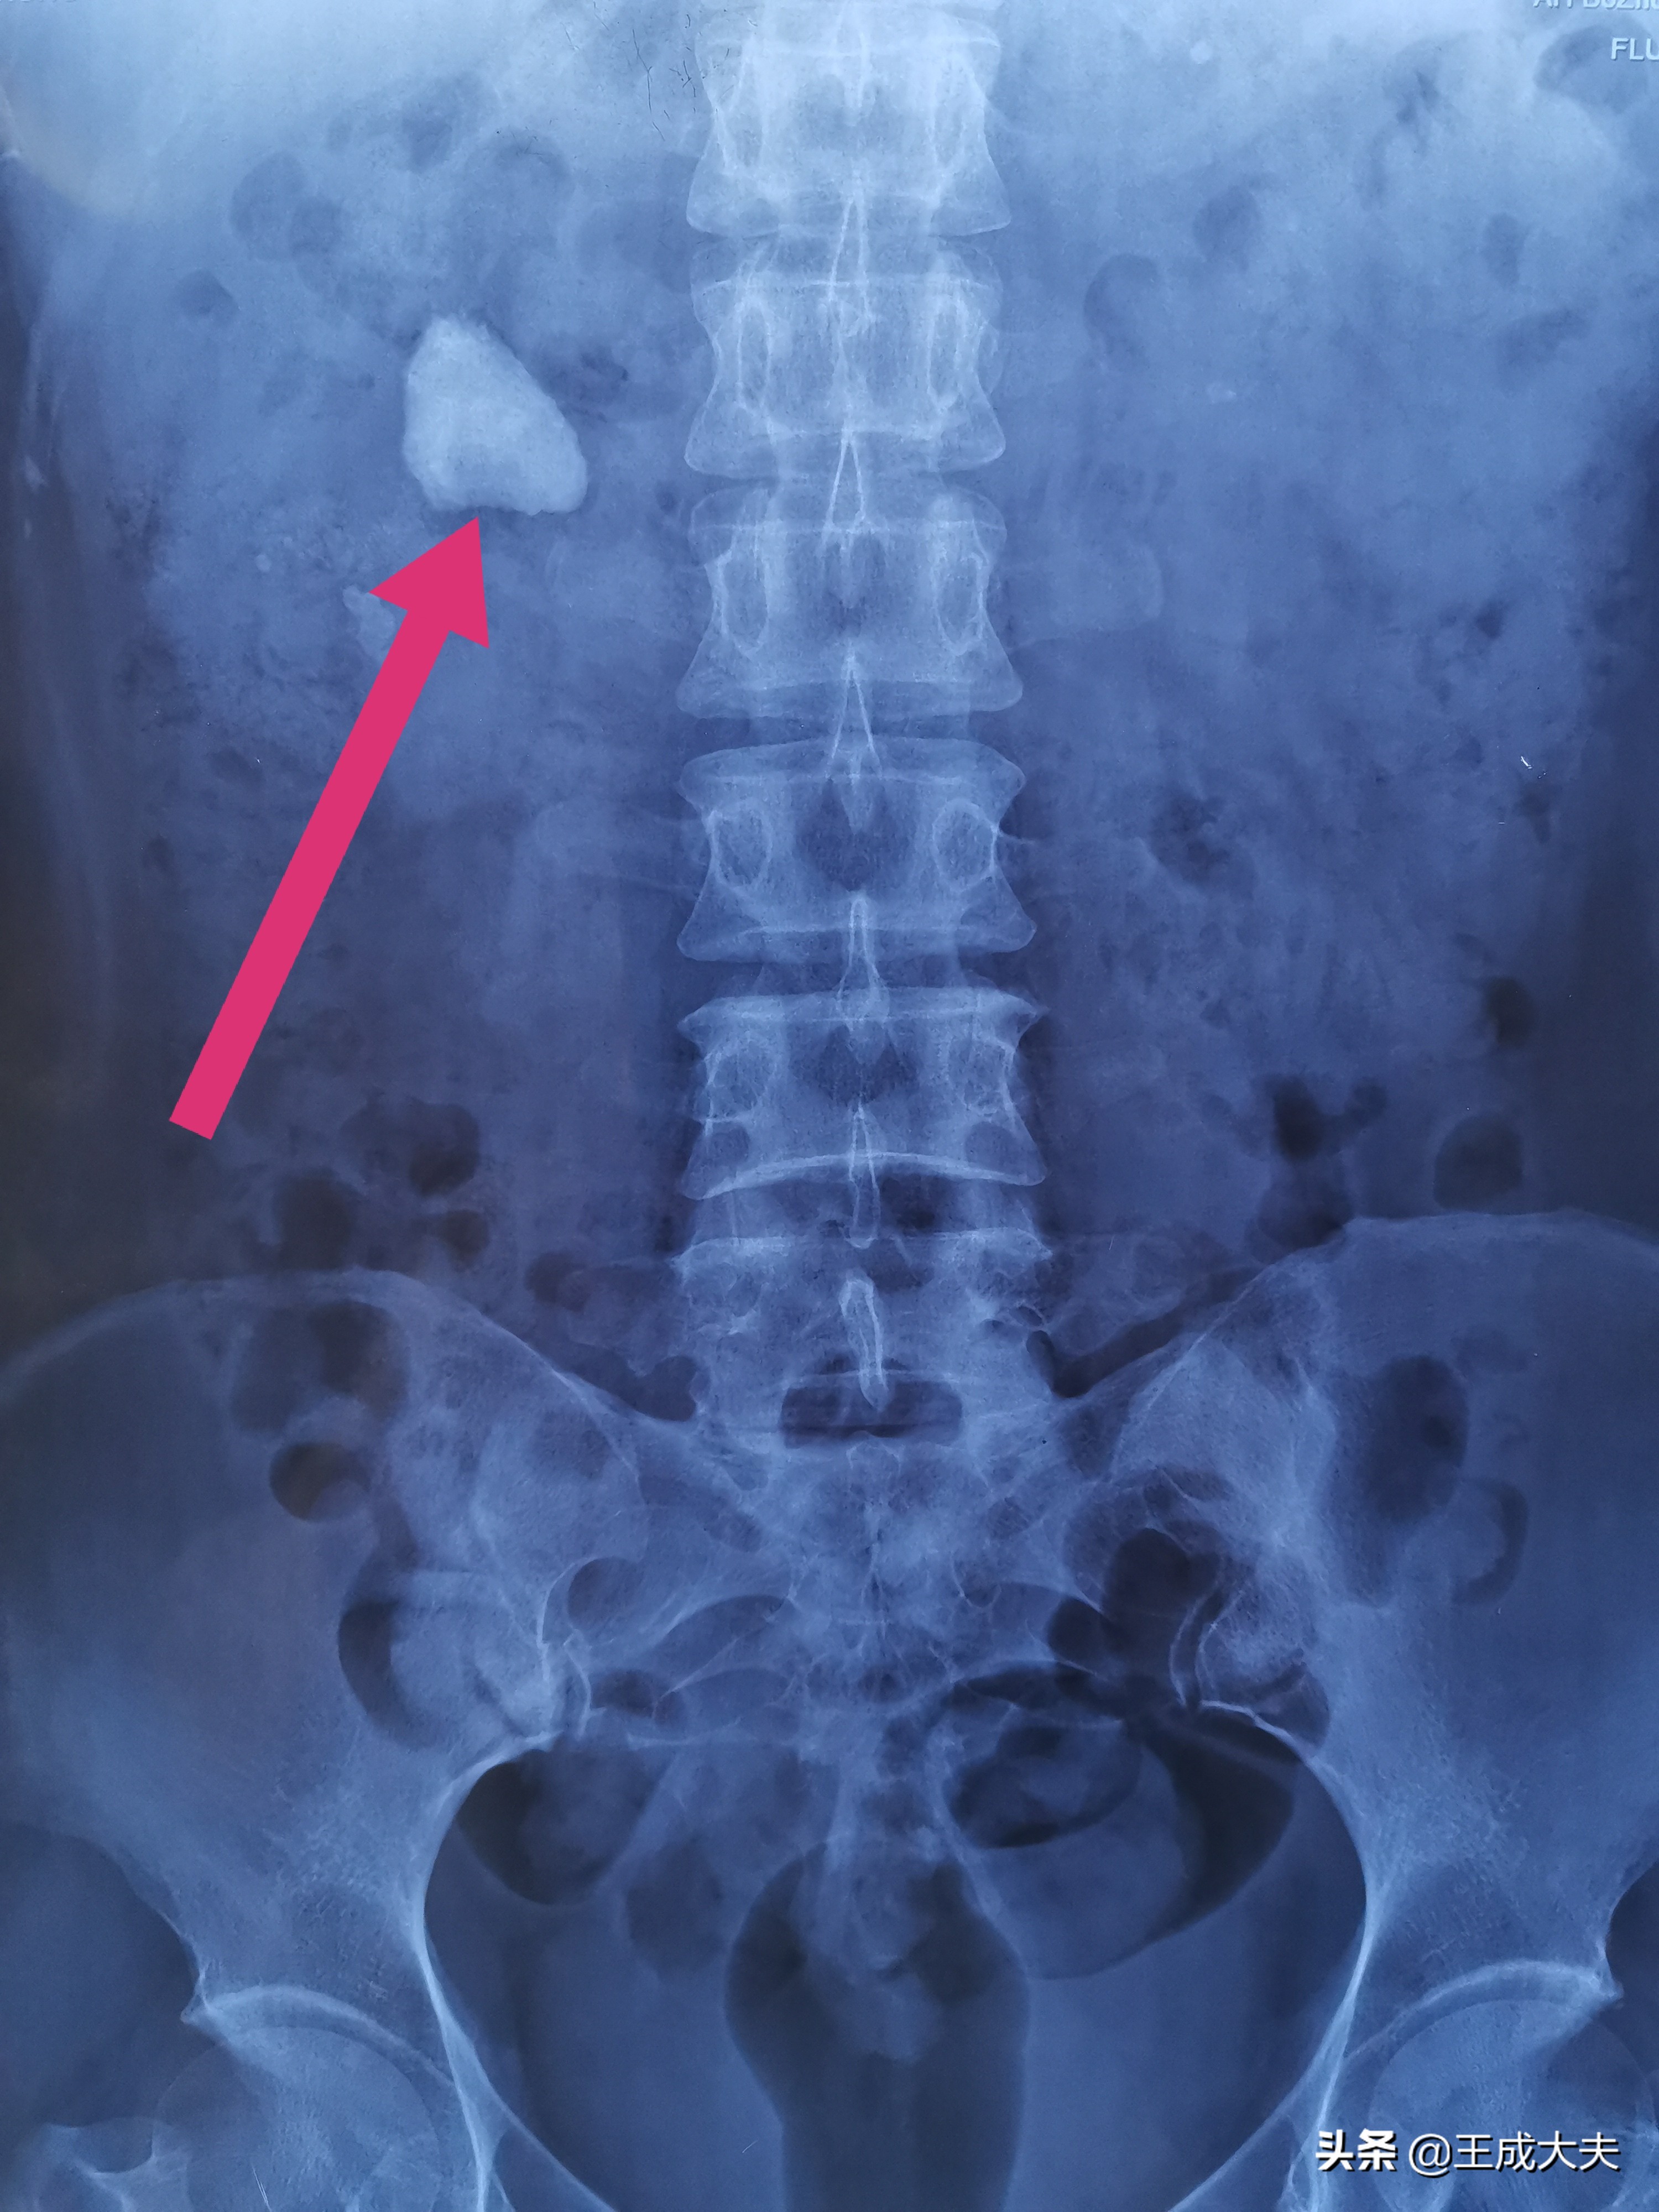

腹部X线片提示右肾门结石